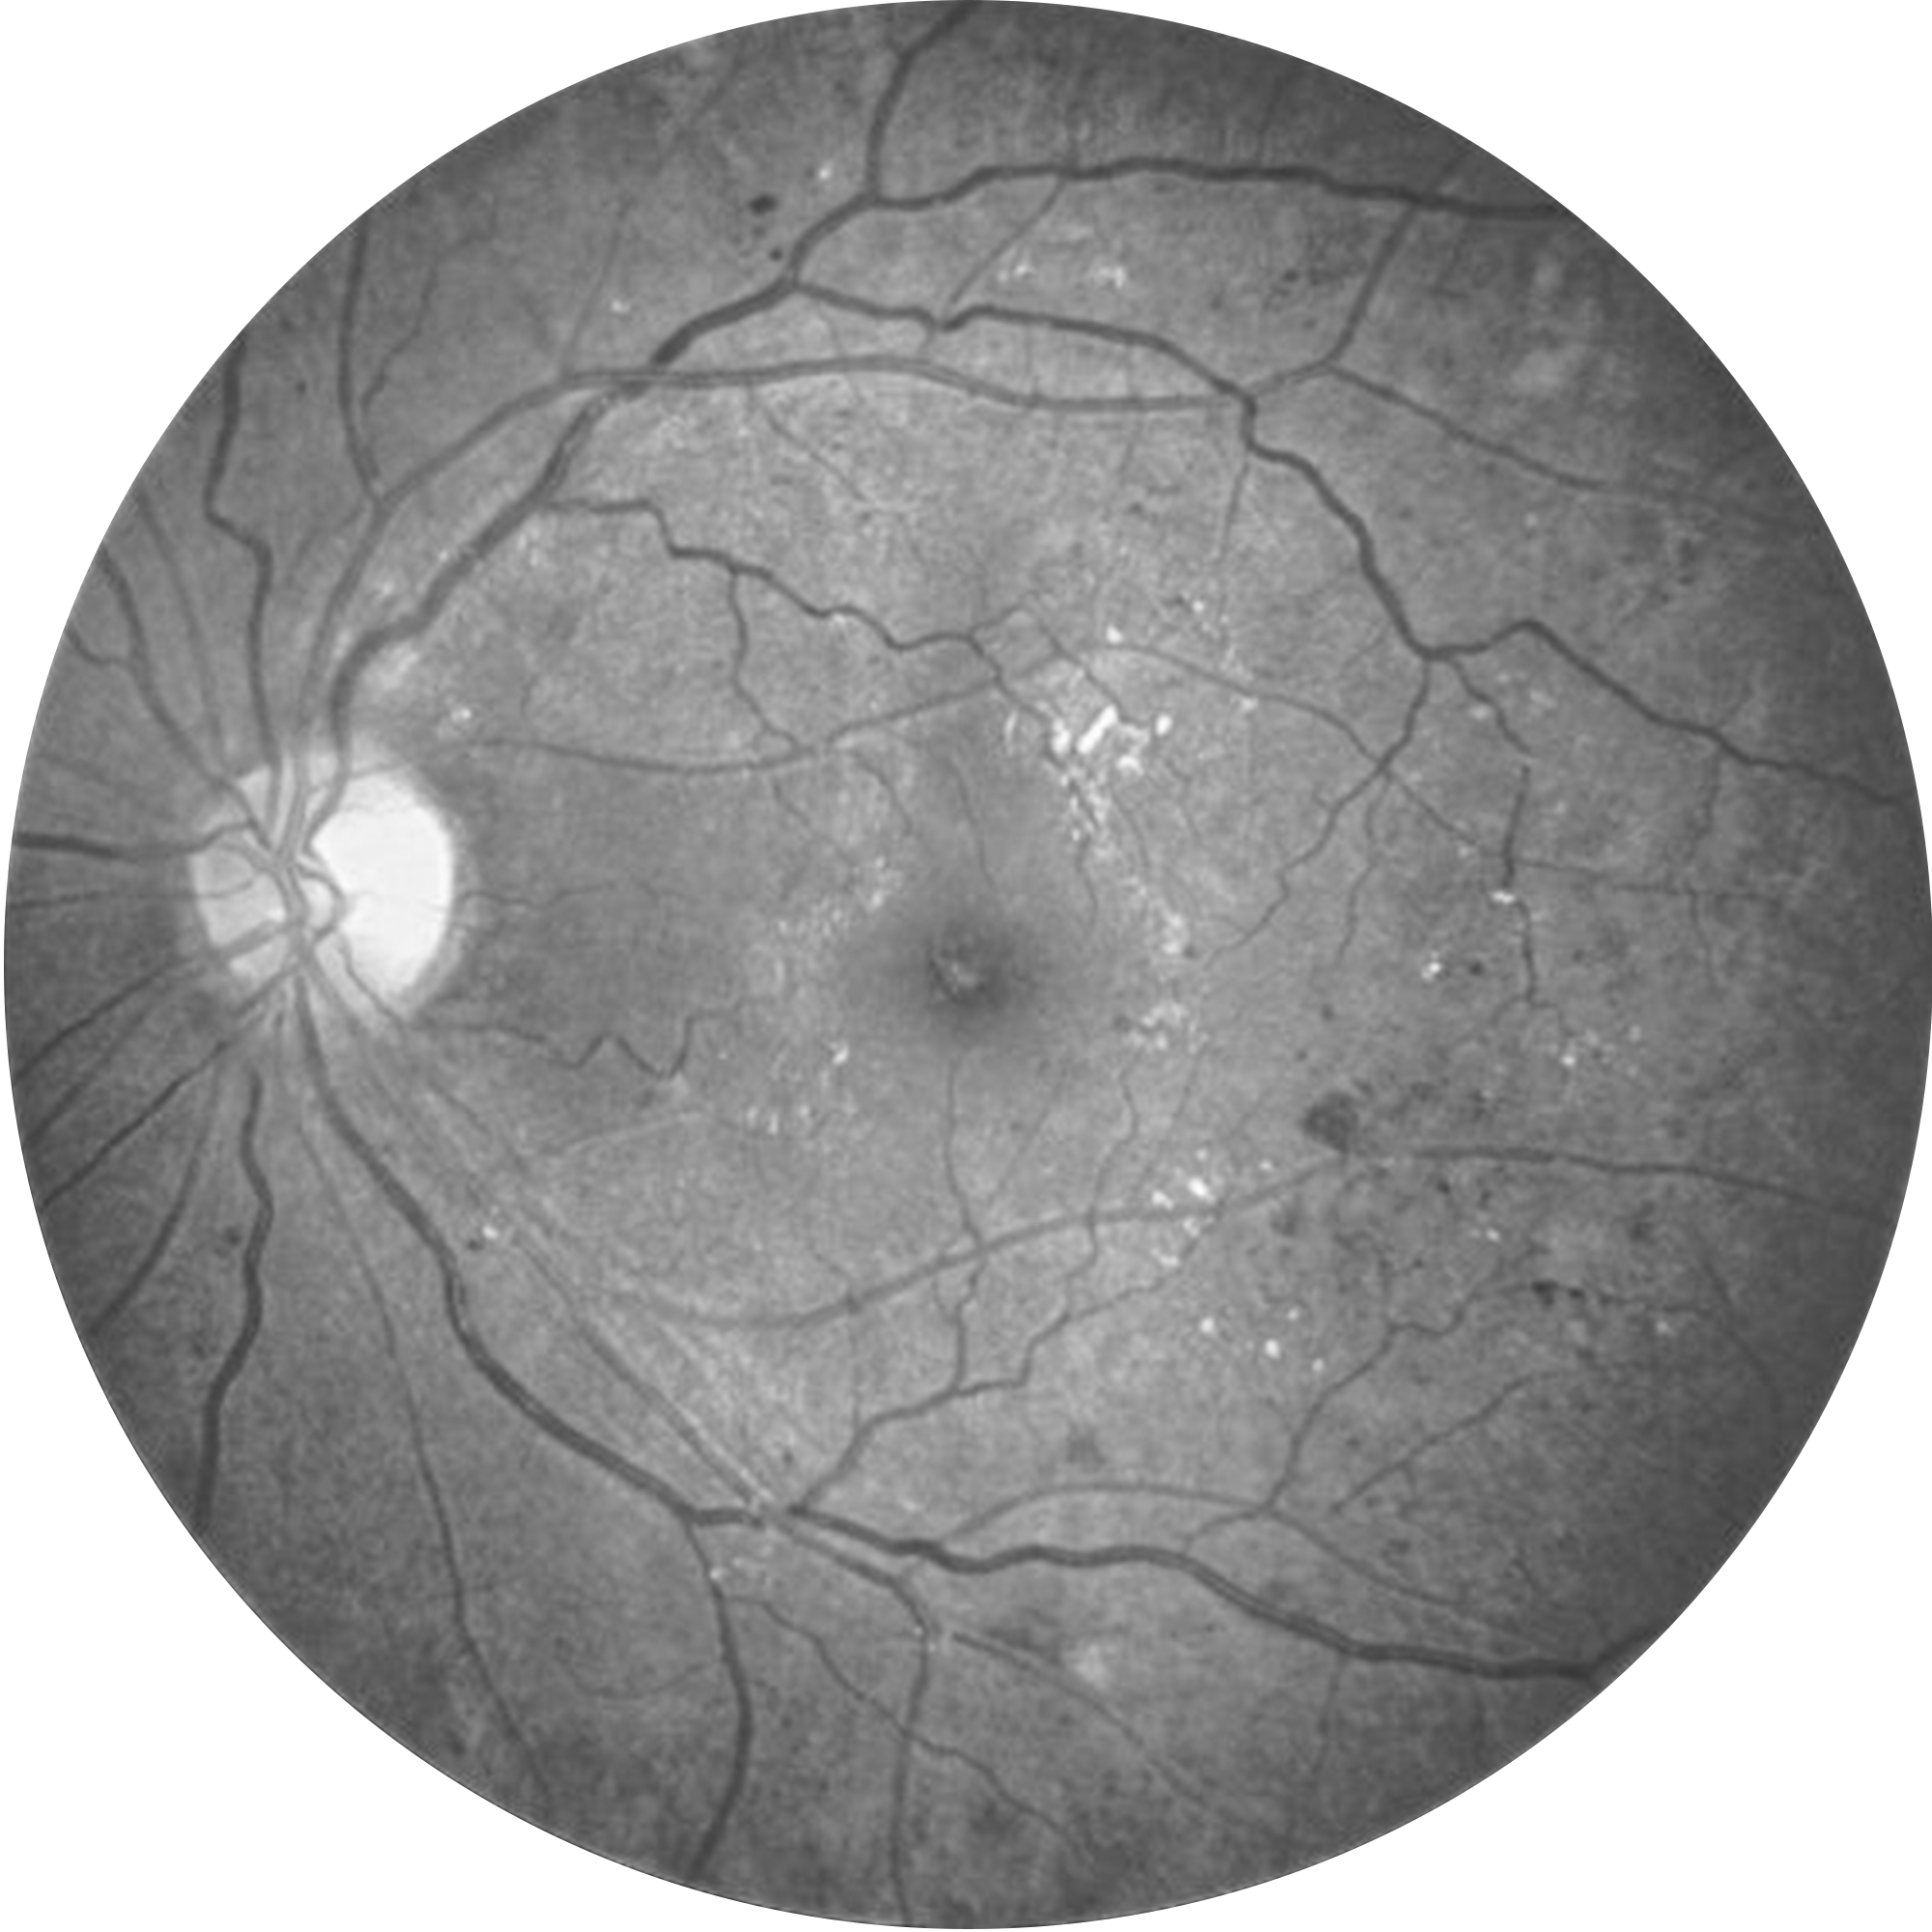

Delivering crystal-clear, high contrast retinal images with a 45° field of view in single shot, and montage to reach the periphery.

Providing retinal images with 2 different imaging modalities

TrueColor, Red-Free Retinal Imaging